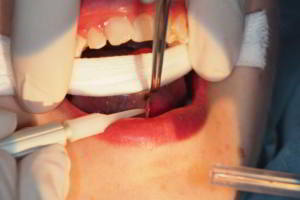

· Imagen 1, leer más...

La cirugía periapical es un procedimiento quirúrgico que tiene como objetivo la remoción de un granuloma o quiste apical con la consiguiente extirpación de la porción apical del diente afectado (apicetomía). En dicha imagen se observa el ápice seccionado y el alveolo remanente que deja la extirpación del tejido infeccioso así como el relleno con MTA del tercio más apical de la raíz del diente endodonciado.